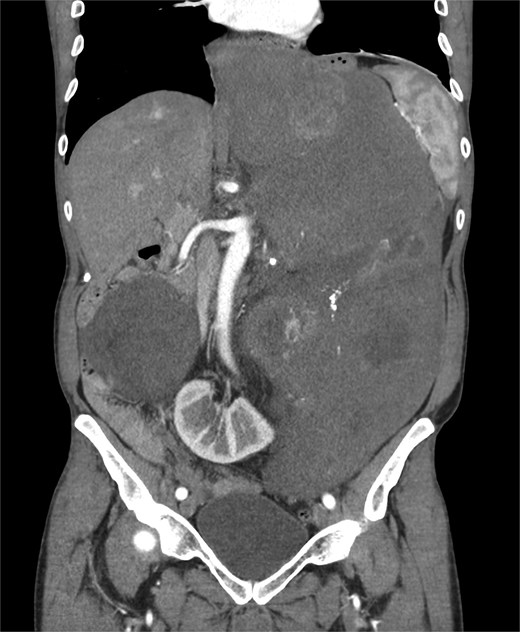

A 53-year-old man, ex-smoker and occasional alcohol consumer, reported several months of postprandial dyspepsia and increased bowel movements (3–4 per day), without weight loss or systemic symptoms. Physical examination revealed a distended, somewhat tense abdomen without focal tenderness. Laboratory tests, including complete blood count, biochemistry, and inflammatory markers, were within normal limits. Cross-sectional imaging demonstrated a multilobulated, predominantly solid retroperitoneal mass measuring 35 × 32 × 18 cm. Contrast-enhanced computed tomography (CT) and magnetic resonance imaging (MRI) showed displacement—but no frank invasion—of the inferior vena cava and aorta, encasement of mesenteric vessels, and compression of bowel loops. A notable anatomic variant was an ectopic left kidney located in the right paramedian pelvis. No distant lesions were identified (Figs 1 and 2). Three-dimensional CT angiography delineated the relationship with major vessels and aided operative planning (Fig. 3). After multidisciplinary discussion, primary surgical resection was favored given the well-circumscribed nature of the mass, the absence of metastatic disease, and the patient’s symptoms. Through a midline xipho-pubic laparotomy, a well-encapsulated, firm, tan-white mass occupying most of the retroperitoneal cavity was exposed. Sharp and blunt dissection allowed complete en bloc excision without capsular violation. Estimated blood loss was modest and no vascular reconstruction was required. Grossly, the specimen weighed approximately 12 kg and showed multinodular architecture with focal myxoid areas.